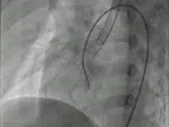

二次术中影像

在术中进行二次超声会诊后,手术团队进行研判,调整了策略,并进行了二次尝试。

建立输送轨道

建立股动脉-VSD-股静脉轨道,沿泥鳅导丝送7F输送鞘至左室,选择6mm对称型、腰高7mm全降解封堵器。

左右盘面展开并锁定

左侧伞盘出鞘为球状,牵拉成型线后形态佳,后展开右盘,封堵器呈现“长哑铃状”,主动脉瓣少量反流。

轻轻牵拉成型线使封堵器成型,牵拉后左伞盘被拉进瘤腔内。

左右盘展开后,封堵器未锁定时造影可见封堵器中间少量反流,主动脉瓣少量反流。

牵拉成型线锁定后,分流消失,主动脉瓣反流消失。

封堵器锁定后呈“蝴蝶状”明显盘状形态,室水平分流完全消失,主动脉瓣反流消失。